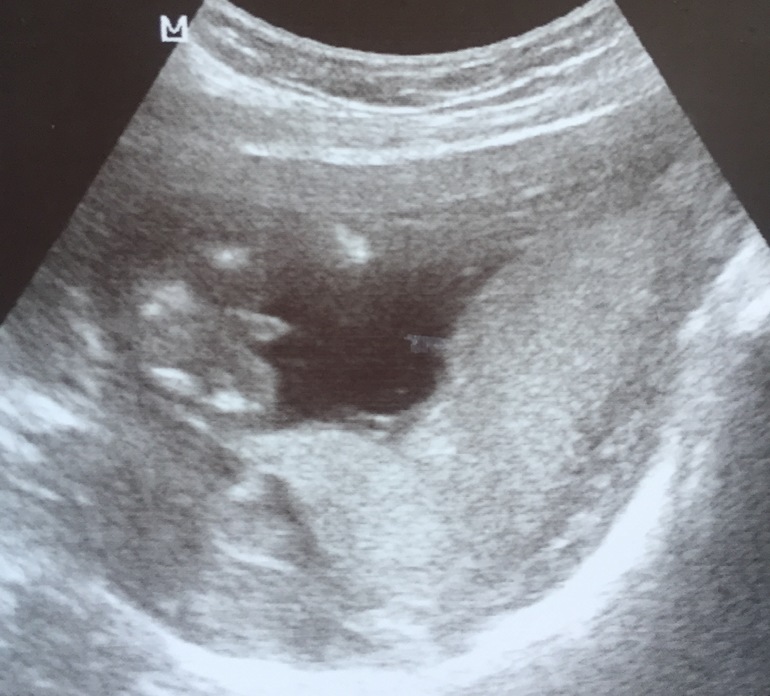

Доча 15с чем то нед. точно не помню.